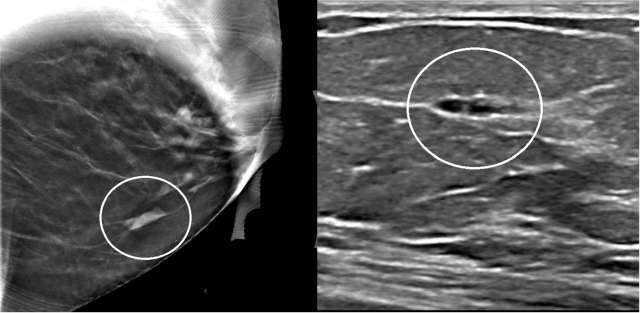

Case: Atypical Ductal Hyperplasia Figure 4

Case 4: Spot MLO view (left) from a diagnostic mammogram demonstrates an asymmetry measuring 10 mm in the left lower breast at anterior depth. A correlation on the CC view (not shown) was not found. Subsequent targeted ultrasound (right) demonstrates a possible cluster of microcysts versus a solid hypoechoic mass at 7 o’clock located 2 centimeters from the nipple, with circumscribed and possible indistinct margins and which corresponded to the mammographic finding. Pathology demonstrated atypical ductal hyperplasia, flat epithelial atypia, and pseudoangiomatous stromal hyperplasia.